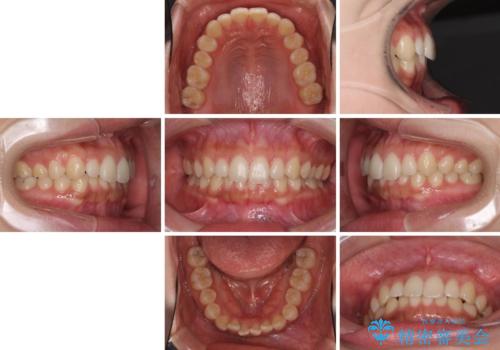

海外勤務中でも矯正治療 インビザラインによる軽度叢生改善

- 前歯のデコボコを気にして来院された患者様です。

治療期間中に海外勤務になる可能性が高いことが分かっていましたが、矯正治療を始めたいとのことでしたので、インビザラインを用いて治療することとしました。

通常であれば半年から10ヶ月程度で終了する歯並びでしたが、海外に長期出張することになったため、1年10ヶ月の期間を要しました。

出張に行かれてしまうと追加のマウスピースを発注できないため、マウスピースの交換頻度を低くし、一時帰国のタイミングに合わせていくことで、スムーズに進めて行くことができました。